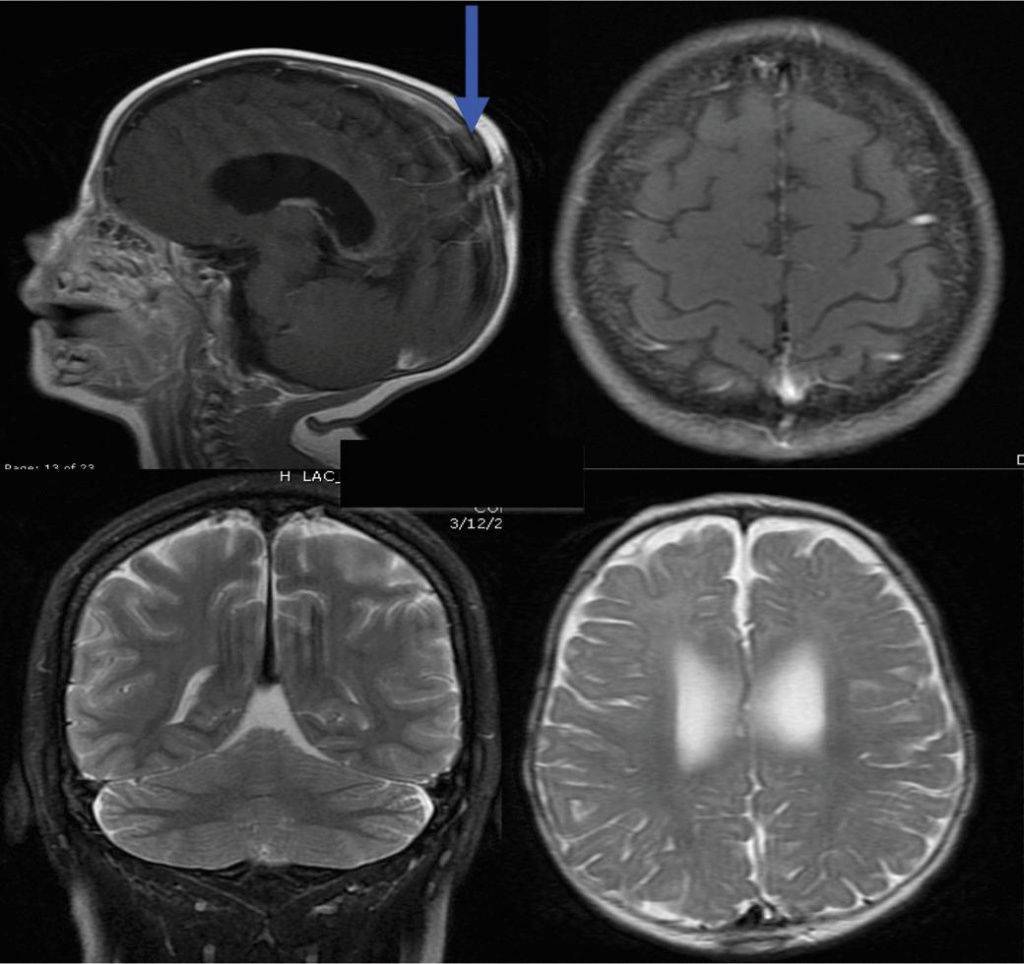

Что показывает МРТ головного мозга

Получив 3D-изображения головного мозга в разных проекциях, врач имеет возможность рассмотреть в деталях каждую его область. Это позволяет сделать выводы о:

Если результаты оказались недостаточно точными или требуется дополнительная визуализация определенного участка, может быть назначена МРТ головного мозга с контрастированием. Введение контрастирующего препарата позволяет получить более точное представление о строении ткани мозга или патологического образования, уточнить его границы.